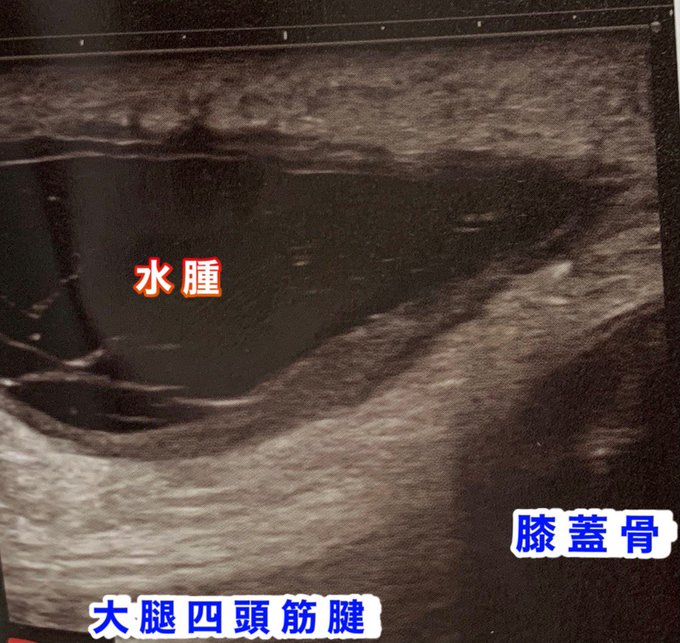

膝の水腫はどれくらい溜まるとballottementが徒手的にわかるのか?

どれくらい溜まったら機能的な障害がでるか?

水腫による痛みのメカニズムは?

抜くと癖になるってほんと?

実態の人体解剖で注射器に関節包に注入して調べた。〇〇ccからわかり、〇〇ccでロッキングした。

今日勉強会します。